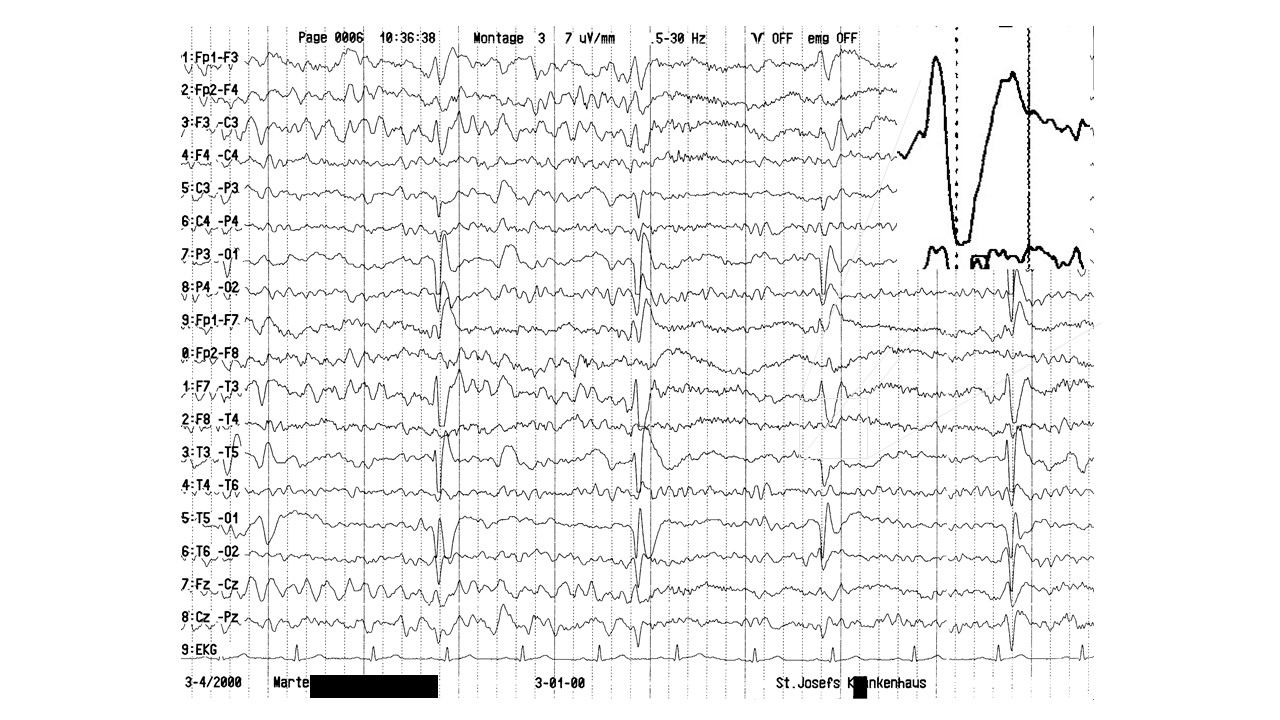

EEG-Seminar III | 64.69 zurück | weiter

folie65.jpg